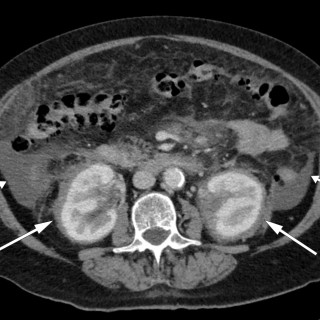

Magesmerter hos barn er en hyppig årsak til henvisning til barnemedisinsk og kirurgisk spesialisthelsetjeneste. Akutt appendisitt, obstipasjon og gastroøsofageal refluks er blant de vanligste diagnosene. Ofte kan barn ha diffuse symptomer, og selv om «det vanligste er det vanligste», er det viktig å være oppmerksom på symptomer som tyder på alvorlig, underliggende patologi. Tett samarbeid mellom fastlege, barnelege, barnekirurg og radiolog kan være viktig for å komme til målet. En jente tidlig i tenårene hadde vært plaget av «treg mage» siden småbarnsalder og hadde gjennom de siste fem årene...